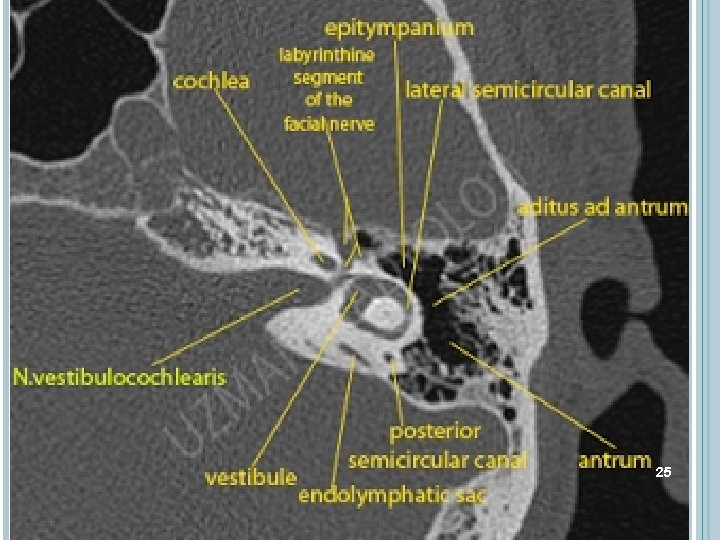

ANATOMİ 3)Labirenter segment: Fasiyal sinir petröz kemik eksenine hemen dik bir seyirle kemiğin üst yüzünün hemen altına kadar sokulur. Burada birinci dirseğini yaparak geri döner ve bu segment genikulat ganglion ile son bulur. Labirenter segmentin uzunluğu 35 mm. kadardır. Burada sinir kokleanın 1. turu ve superior semisirküler kanal ile komşu olduğundan bu kısma labirenter segment adı verilir. Burası 0, 68 mm çapıyla fasiyal kanalın en dar kısmı olup, sinirin travma veya enflamatuar hadiselerden en çok etkilenen bölgesidir. 13

ANATOMİ 4) Timpanik segment: Timpanik parça 10 -12 mm. uzunluğunda olup proksimal ucu genikulat ganglion ile sınırlanmıştır. Horizontal parça adını da alır. Bu segment fasiyal sinirin orta kulakla komşuluk yaptığı kısımdır ve Luntz ve ark. yaptığı çalışmada burada sinirin incus kısa kolunun en posterioruna olan mesafesini ortalama 3. 31 mm olarak bildirmişlerdir. Piramidal çıkıntıyla komşuluk yaptığı yerde fasiyal sinir üçüncü olarak stapes dalını verir. Bu dal stapes kasını innerve eder. Piramidal çıkıntının hemen distalinde fallop kanalı birincisine göre daha geniş ve aşağıya doğru ikinci bir dirsek yapar. 15

ANATOMİ 4) Timpanik segment: Fasiyal kanalın 2. ve 3. segmentleri arasındaki açı 95 -125 derece arasında değişir. Bu 2. dirseğin konveksliği arkadan posterior semisirküler kanal ve posterior kraniyal fossa ile ilişkilidir. Üstte ise lateral semisirküler kanalın yayı bulunur, ancak fasiyal kanal arkaya yönelerek ondan uzaklaşır. 16